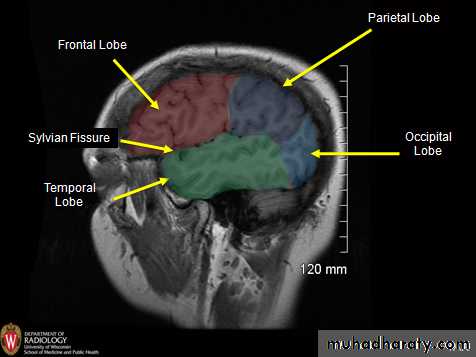

• lobeS :

• 1. Frontal lobe (in front of the central sulcus• and above the lateral sulcus),

• 2. Temporal lobe(below the lateral sulcus),

• 3. Parietal lobe (behind the central sulcus and

• above the lateral sulcus),

• 4. Occipital lobes (behind the parieto-occipital

• sulcus).

• 5. Insula

Lobes of Cerebral Hemisphere

Five lobes

Frontal lobe

Parietal lobe

Temporal lobe

Occipital lobe

Insular lobe

Parietal lobeOccipital lobe